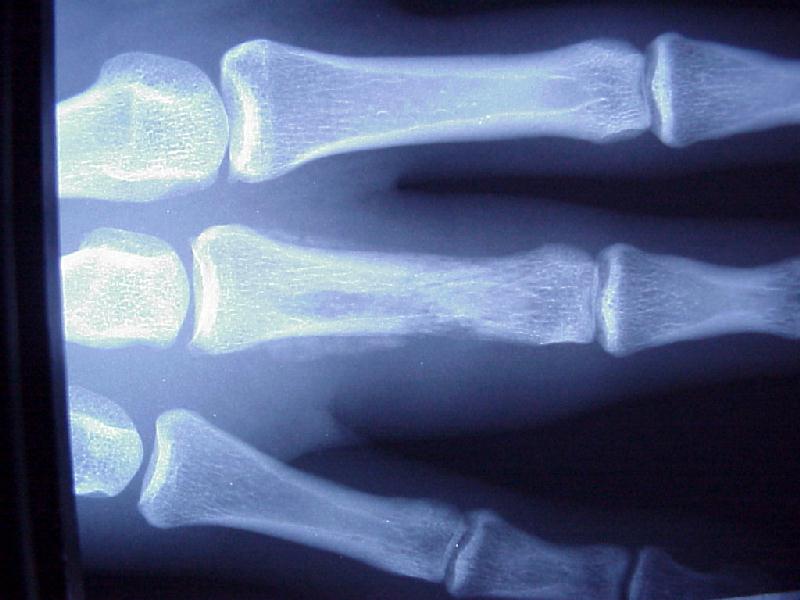

Clenched fist bite injury 12 hours old, rapidly progressive infection and divot in metacarpal head.